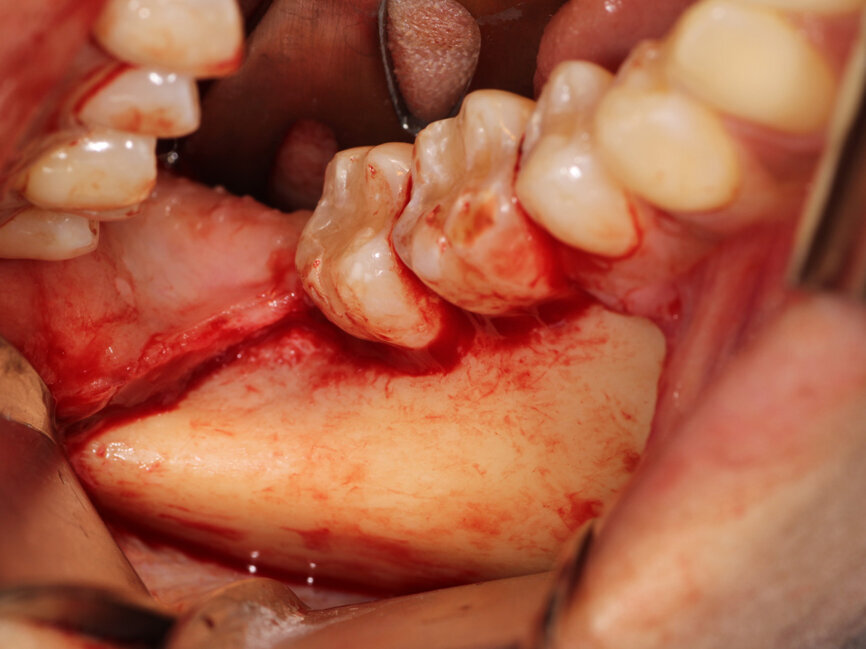

Fig. 3: A full thickness flap was created to expose the deficient facial aspect of the edentulous premaxilla that will receive augmentation to accommodate implant placement.

A #15 scalpel was utilized to create a vertical releasing incision between the right canine and lateral incisors and also between the left first and second premolars. These were connected by a facial sulcular incision medial to the vertical releasing incisions and a midcrestal incision at the edentulous area. A full thickness flap was elevated extending past the mucogingival junction to exposure the deficient area as well as bone covering the roots of the adjacent teeth (Fig. 3). A thin ridge with a notable concavity at the edentulous area was confirmed correlating with what was accessed on the CBCT exam. A three sided 1.2 mm bur from MedEquip Dental Supplies in a surgical handpiece was utilized to create multiple decortication points through the cortical bone to the underlying cancellous bone (Fig. 4). This is performed to allow endosteal osteoblasts from the cancellous bone to interact with the graft, grow bone around and within the particulate graft particle, and to accelerate vascularization of the graft and incorporation to the osseous bed.